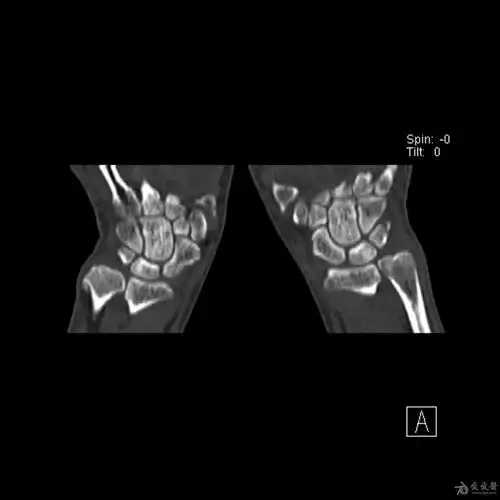

腕部三角骨骨折

舟骨三角骨骨折及月骨周围脱位 - 知乎